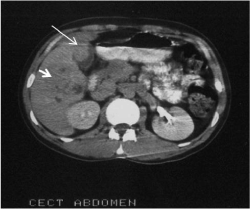

Ultrasound of the patient revealed a mass of mixed echogenicity arising from the anterior wall of the gall bladder (GB) and invading the liver (Figure 1). Another mass predominantly hypoechoic with non-homogenous internal echoes was found in proximity to the first mass, in right lobe of liver. Computed tomography showed a polypoidal mass arising from the anterior wall of the GB and protruding into the lumen (Figure 2). Mass was also extending into the adjacent area of the liver. On the right side of the GB, another focal mass of variegated appearance was seen. A probable diagnosis of carcinoma of the gall-bladder with a secondary in liver was suggested.

Figure 1. US Picture showing GB mass invading the Liver. Another mass is seen in right lobe of Liver (GB- Gall bladder; M- mass)